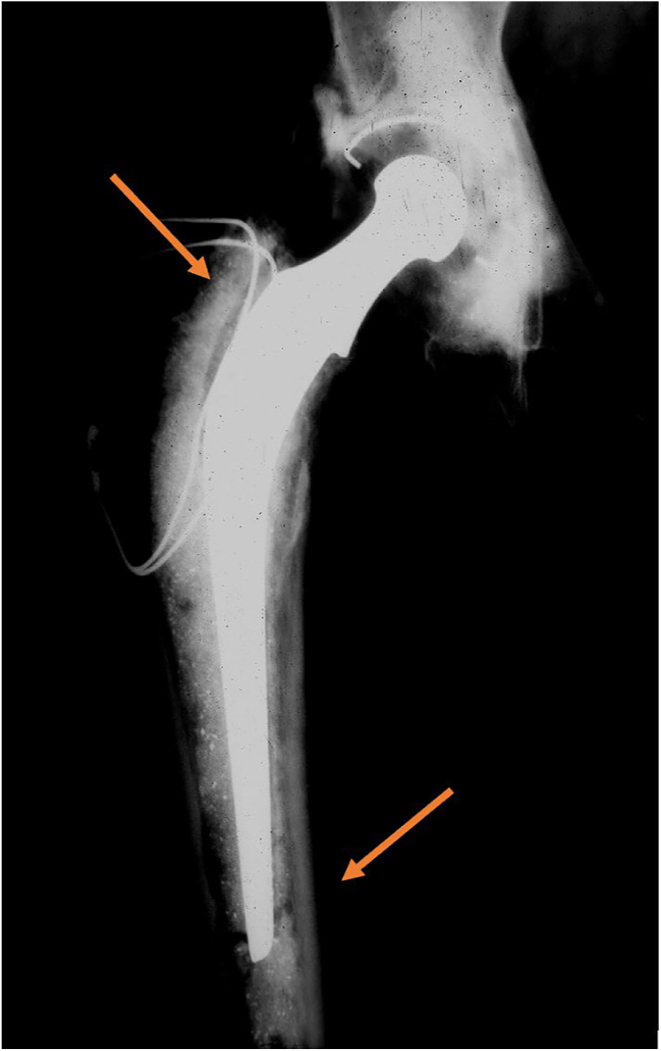

The French paradox cementing technique encompasses a canal filling highly polished stem with a thin (<1 mm) cement mantle. The technique has been developed by Pr Marcel Kerboull in the late 1960s after he observed the patterns of debonding of the original Charnley stem. The key point of the technique is based upon removal of the metaphyseal cancellous bone (with hollow reamers or aggressive broaches) especially at the supero-medial region. Only two stems have been validated with this technique: the Charnley-Kerboull (CK) and the Ceraver Osteal stem, both of which are collared. This technique is neither a taper slip (the stem does not subside at long-term follow-up) nor a composite beam (a highly polished stem is used). A 12% shortened stem CK has shown similar results to the standard-length stem, including the absence of stem subsidence. Combined with the Hueter anterior approach, this technique has demonstrated one of the lowest femoral PPF rate in elderly patients in the literature.